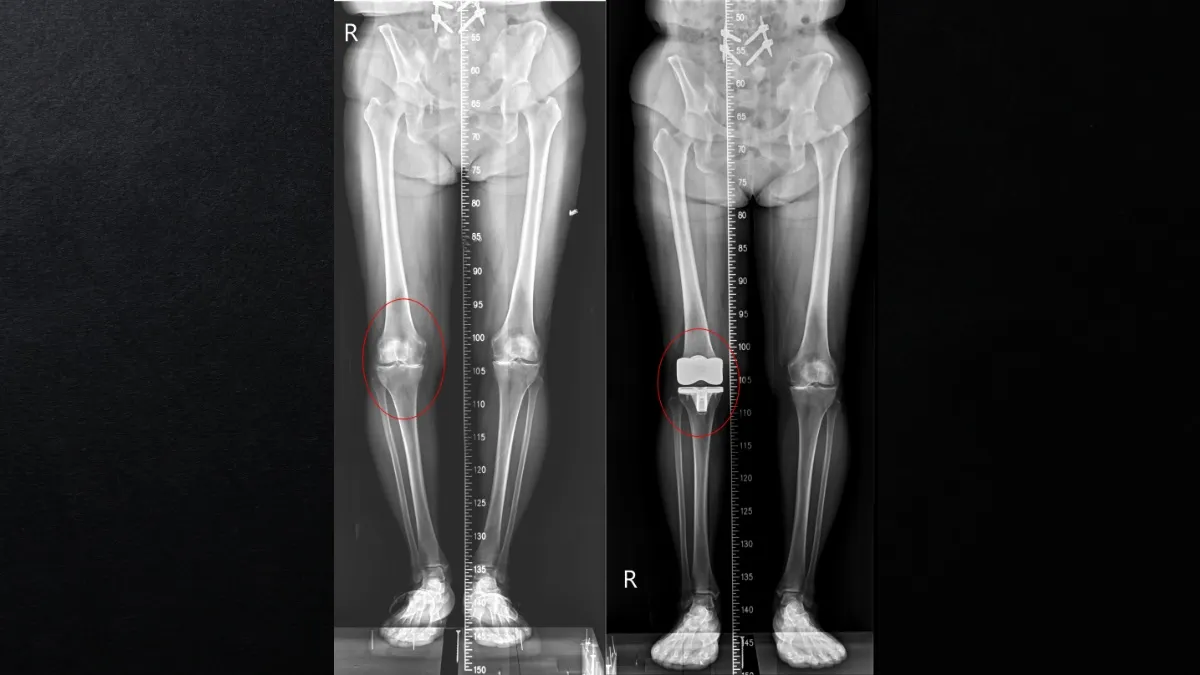

久站痛到軟腳!63歲餐飲大姐「換膝蓋」免鋸骨 醫曝這手術隔天就能走

一名從事餐飲業多年的63歲女性,因長期久站導致雙膝嚴重退化,走路不到5分鐘就得休息,甚至頻繁出現「軟腳」、無法伸直等症狀